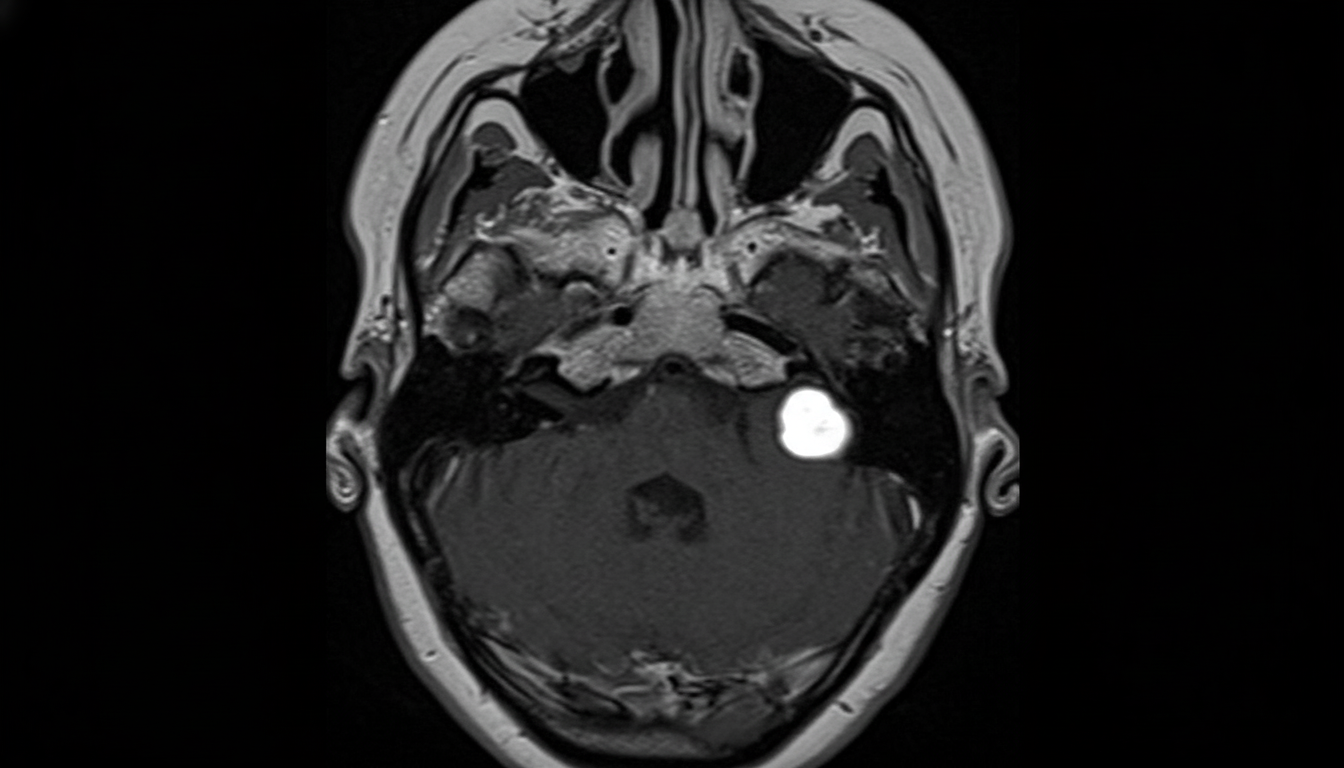

Explanation: ***Acoustic neuroma*** - **Acoustic neuroma** (vestibular schwannoma) commonly presents with **unilateral tinnitus** in elderly patients, often as the first symptom before hearing loss develops. - **MRI findings** typically show a **mass in the internal auditory canal (IAC)** or **cerebellopontine angle (CPA)**, which is characteristic for this benign tumor. *Acute suppurative otitis media (ASOM)* - ASOM typically presents with **acute ear pain**, **fever**, and **purulent discharge**, which are not mentioned in this case. - More common in **children** and usually associated with **recent upper respiratory tract infection**. *Labyrinthitis* - Primarily presents with **acute vertigo** and **nausea/vomiting** rather than isolated tinnitus as the main symptom. - Usually follows **viral infection** and symptoms are typically **self-limiting** within days to weeks. *Acoustic trauma* - Results from **sudden loud noise exposure** or **chronic noise exposure** causing immediate hearing damage. - Would have a **clear history of noise exposure** and typically presents with **sudden hearing loss** rather than gradual onset in elderly patients.